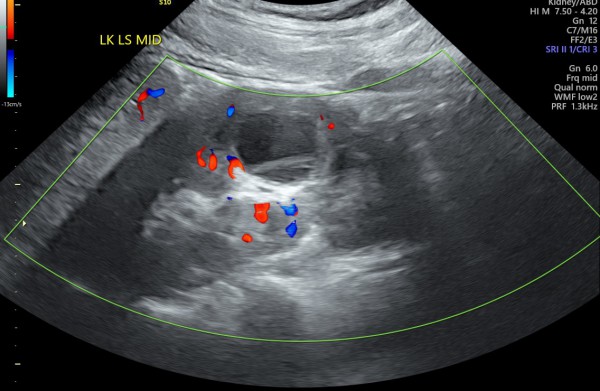

Czy mógłby ktoś mi powiedzieć czy 'infekcja cysty' to poprawna interpretacja załączonego USG?